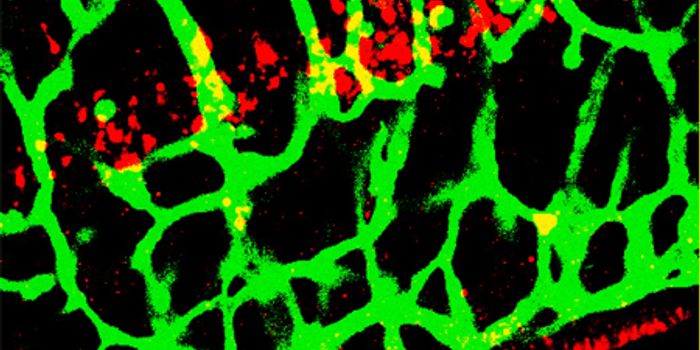

JAN 07, 2022CancerThe blood-brain barrier (BBB) describes the complex vasculature network that delivers oxygen and nutrients to the brain. ...